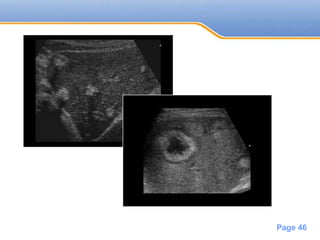

• #46 cystic squamous cell carcinoma ovarian cancer pancreatic adenocarcinoma colorectal carcinoma (CRC)

• #47 Calcified liver metastases of a sigmoid carcinoma with hyperechoic lesions causing acoustic shadowing Liver metastases with central necrosis